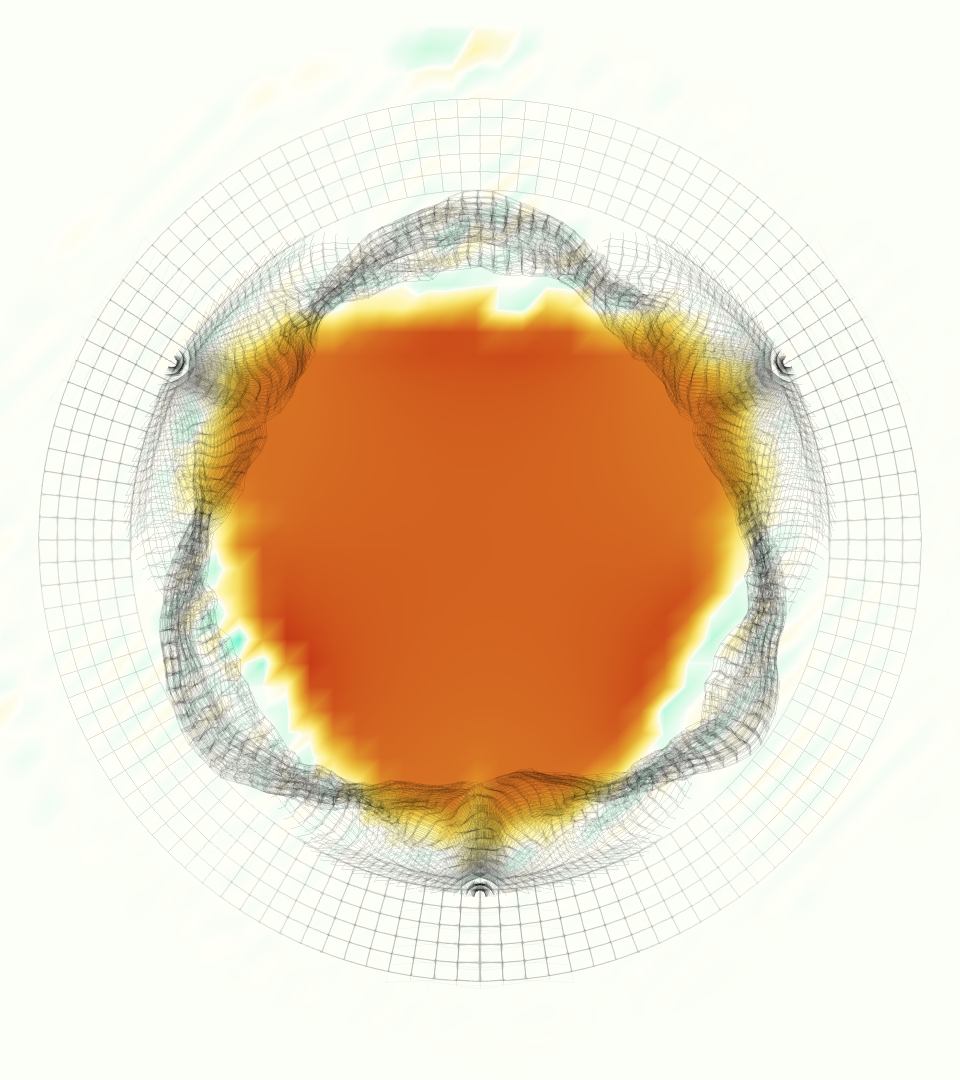

At = 0, the axial slice directly at the valve annulus shown in columns 1 and 2 in Figure 6, there was excellent agreement between the simulation and experiment over the cardiac cycle in the speed and shape of the jet through the valve. In both cases, the axial velocity increased as the flow accelerated during systole and the valve leaflets opened, then decreased during diastole with slight negative velocity before the valve leaflets were fully closed. The forward flow through the valve annulus did not form a full circle, but rather developed a triangular shape with a point of the triangle forming along the interior curve of the vessel, at the bottom of the axial slices. At = 0, the points of this triangular jet shape aligned with the commissures of the valve. This shape persisted during peak systole and was well-matched by the simulation.

The axial slice = 0.625 cm, shown in columns 3 and 4 in Figure 6, cut through the support scaffolding of the valve and the leaflets when they are open. In the experimental data, the shape of the jet changed as it moved downstream. A triangular shape occurred, but the points were then aligned with the middle of each open leaflet as opposed to the commissures. Those points were also more rounded than they were at = 0. The peak velocity of the jet was faster at = 0.625 cm than at = 0, as the flow accelerated through the open valve leaflets. The simulation produced these features at = 0.625 cm. The triangular shape of the jet shifted similarly, and its speed increased compared to the upstream slice. As the flow decelerated into diastole, the jet shape remained roughly triangular but diminished in intensity before disappearing after valve closure.

The jet continued to develop at = 1.25 cm, an axial slice immediately downstream of the valve scaffolding and open leaflets, shown in columns 5 and 6 in Figure 6. In the experimental data, the points of the triangular jet shape extended further towards the vessel wall. In addition, regions of reversed flow developed in the locations downstream of the commissures, resulting in curved sides to the shape of the jet. Each tip of the jet was unique, due to variations in the individual leaflets in the physical bioprosthetic valve. These variations are apparent in the velocity fields, possibly because the jet edges are similar enough cycle to cycle that irregularities are still being captured even with phase averaging. Further discussion of these features can be found in Schiavone et al. [39], which showed that the jet tip shapes occurred in different pulmonary anatomies, demonstrating that they were likely due to inherent properties of each leaflet. The leaflets in the mathematical model of the valve are identical, so these nuances in leaflet variation could not be replicated. The simulation did capture some of the extension of the tips of the jet, as they were closer to vessel wall at slice = 1.25 cm than = 0.625 cm. The curves in the triangular sides of the jet were also present in the simulation, though they were less pronounced than the experimental data. At both = 0.625 cm and = 1.25 cm, the jet shape in the simulation was smoother than the jet in experiment. It is possible that the free edges of the leaflets in the mathematical model are not fully replicating the behavior of the physical leaflets of the bioprosthetic valve, in particular the amplitude or frequency of leaflet flutter, leading to the variations seen in the jet shape at = 1.25 cm downstream of the leaflet edges. The simulation, however, does capture the key features of the triangular shape and speed of the jet. Overall, qualitative comparisons demonstrated that the simulation reproduced key features of the flow during systole and diastole.